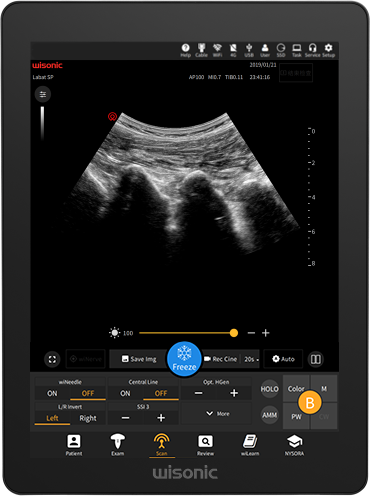

wiNerve AI Intelligent Nerve Recognition

Real-time Recognition

Support Multiple Nerves

wiNeedle – Intelligent Needle Enhancement Technology

Automatic beam steering

Intelligent needle tip and shaft detection